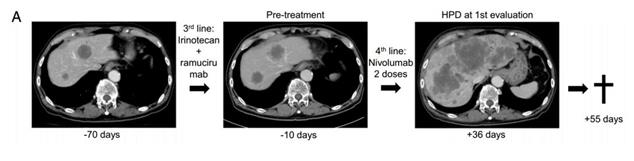

按照HPD的定义,治疗两个月内,肿瘤符合增加50%以上,进展速度增加1倍,这17人里有4人(11.1%)被诊断为HPD。尽管开始治疗之前,他们的身体状态都不错,但是非常短的时间内(20-65天),就有3名HPD患者死亡,大多数HPD患者都发生了多发性转移。

HPD患者肿瘤迅速发展